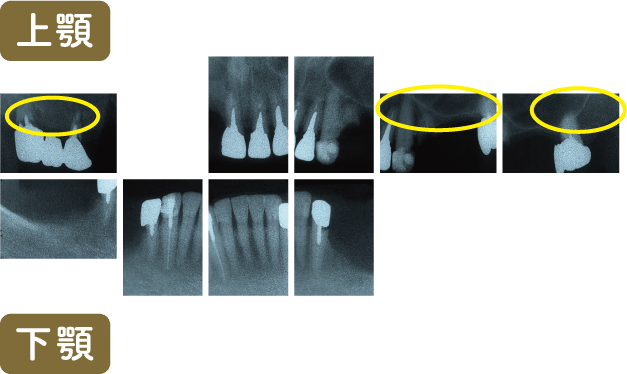

■術前レントゲン写真

上顎の臼歯(奥歯)は歯周病や根の先端が化膿していることから重症であることがわかります

また義歯の支台歯(義歯のバネがかかる歯)にも大きな歯周病が生じています